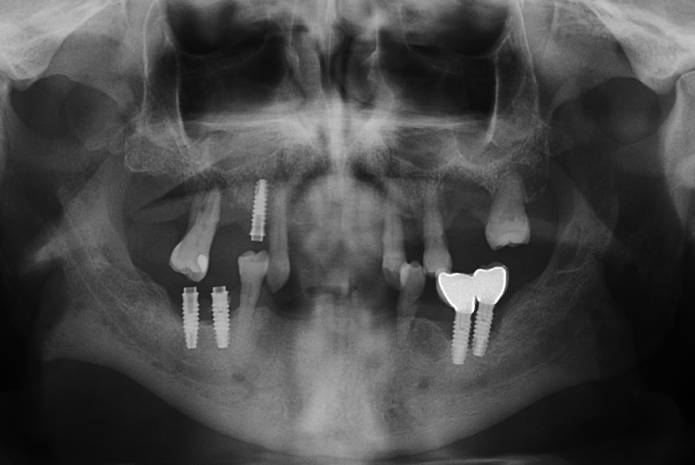

En el presente caso clínico se describe una rehabilitación bimaxilar sobre implantes. El diagnóstico y plan de tratamiento se establecieron a partir de registros fotográficos, escaneados intraorales y Tomografías computarizadas de haz cónico (CBCT), que permitieron una planificación integral del caso. Por motivos académicos, se incorporó un flujo analógico en el diseño y la confección de las prótesis provisionales, utilizadas durante varios meses. Para las prótesis definitivas se empleó un flujo completamente digital, tanto en la comunicación con el laboratorio como en las técnicas de impresión, lo que permitió finalizar el tratamiento en un número reducido de citas y con resultados altamente predecibles.